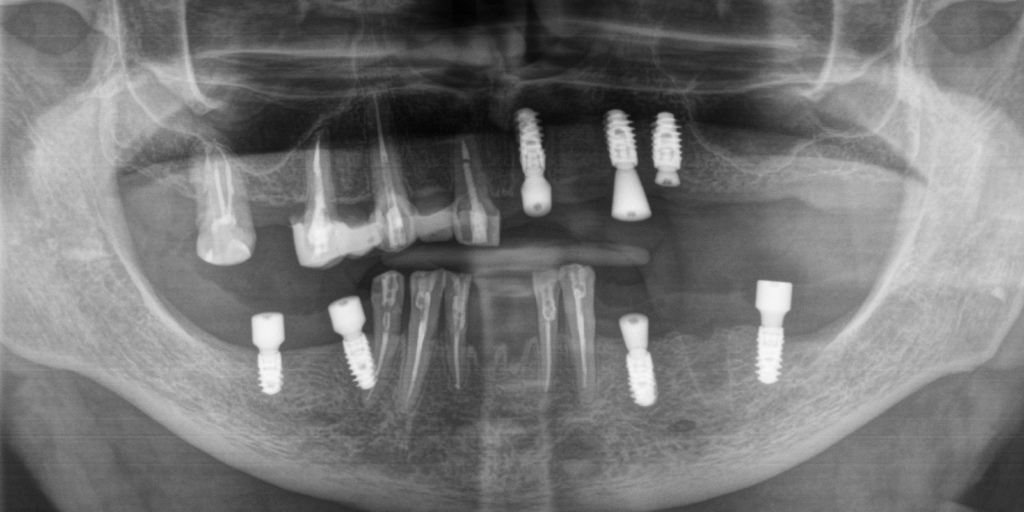

- Установить 7 имплантатов Straumann BLX (3 на верхней челюсти слева, 2 слева внизу, 2 справа внизу).